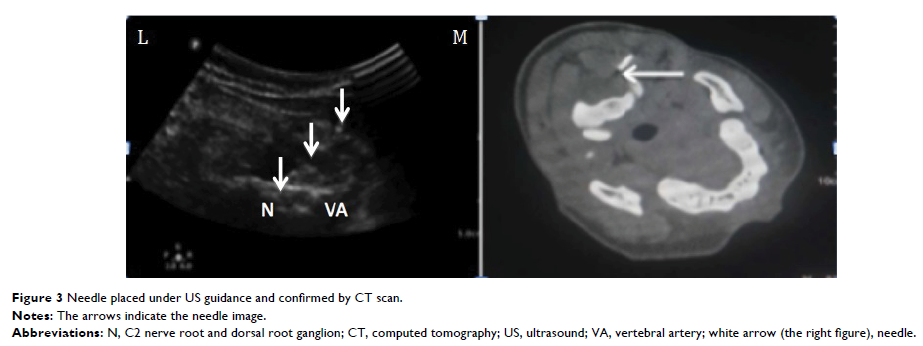

超声引导下的 C2 背根神经节脉冲射频治疗慢性偏头痛:一份病例报告